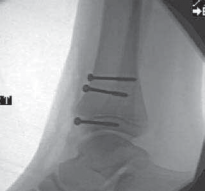

MEDIAL MALLEOLAR FRACTURES: SALTER-HARRIS TYPE III AND IV FRACTURES

1. If there is only a small metaphyseal fragment, these fractures may be fixed with 4.0-mm cancellous bone screws or Kirschner wires completely within the epiphysis and parallel to the physis and joint (

TECH FIG 4

).

1. These fractures can be treated percutaneously if anatomic reduction can be attained by closed treatment; however, a small incision can easily allow direct visualization of the reduction. A BTECH FIG 4 • Medial malleolar fracture fixation with an epiphyseal screw. If there is only a small metaphyseal fragment, medial malleolar fractures can be fixed with compressive screws placed within the epiphysis, parallel to the physis. Cannulated screws can be used to help ensure the physis is not compromised. 23. If a larger metaphyseal fragment is present, another metaphyseal screw can be placed parallel to the physis in addition to the epiphyseal screw.

24. If the patient is skeletally immature and the fracture is not amenable to intraepiphyseal fixation, Kirschner wires may be placed across the fracture site and physis for stability of the fracture and later removed.

1. This method can also be used if there is a small avul-sion fragment off the medial malleolus.

25. If the patient is near skeletal maturity, these fractures can be treated as in adults with two partially threaded cannulated screws placed perpendicular to the fracture site.

1. Alternatively, in this population near maturity, compression across the fracture and apophysis can be obtained with two Kirschner wires compressed by means of a tension band wire loop.